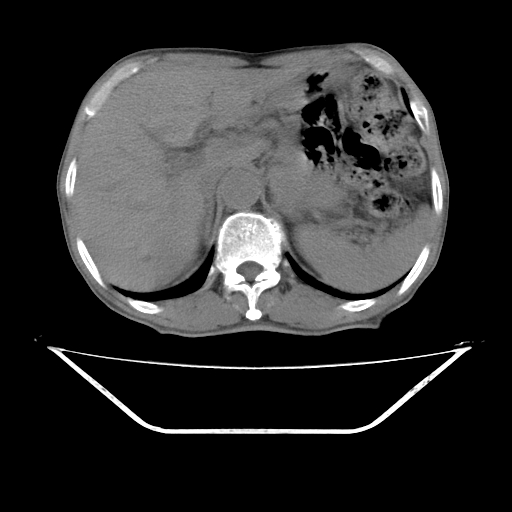

平扫

考虑右肾盂癌,肾动脉受侵,右肾功能减退,右肾盂输尿管积水,管壁增厚,考虑种植转移,应该把下面扫完的

支持右侧肾盂癌伴肾静脉瘤栓形成可能性大,右肾结石.肝右叶后段低密度影,不除外转移.

考虑右肾盂癌,肾动脉受侵,右肾功能减退,右肾盂输尿管积水,管壁增厚,考虑种植转移  支持

右肾囊实性占位,支持肾癌,窗宽窗位不是很理想

右肾盂旁ca并肾静脉瘤栓形成/肾功能降低。

右肾结石。

右肾盂癌,肾动脉受侵,右肾盂输尿管积水,管壁增厚,考虑种植转移

支持 右侧肾盂癌伴肾静脉瘤栓形成可能性大,右肾结石;肝右叶后段低密度影,不除外转移。

1.右侧肾盂癌伴肾盂积水。

2.肾脏功能减退,原因有:(1)肾动脉受侵。(2)肾静脉受侵(3)肾积水,等。本例,肾动脉显影较好,但受压明显;肾静脉无明显显示,受压或静脉癌栓,下腔静脉腔内未见明显充盈缺损。

3.右侧上段输尿管扩张,原因:(1)积水所致;(2)种植。